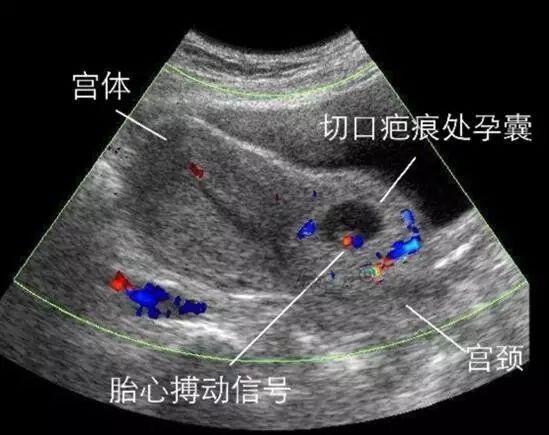

瘢痕妊娠是有瘢痕子宫的女性,再次怀孕后,孕囊着床在子宫原瘢痕处,出现阴道大量出血以及晚期子宫破裂的异常妊娠。

瘢痕子宫是由做过剖宫产、子宫肌瘤剔除、子宫修补、子宫损伤术后使子宫产生细微的裂缝。当有瘢痕子宫的女性怀孕后,孕囊着床在裂缝处,当胚胎发育,会撕裂裂缝,造成子宫破裂、大出血。其凶险性不低于宫外孕,严重者能危机生命。